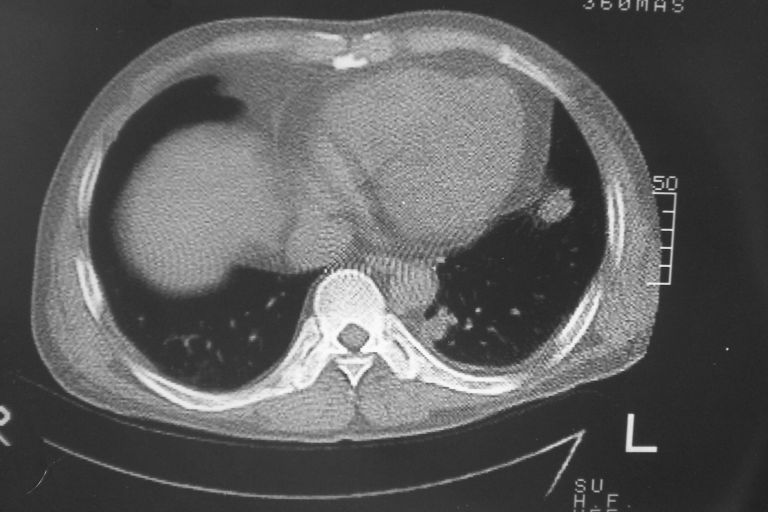

标题: CT10574:男 50岁胸部CT请会诊!

患者 男 50岁 无痛性咯血3天,无其他不适.

左下肺结节状软组织密度影,边缘有毛刺,考虑周围型肺癌。

1 左肺下叶基底段见两结节软组织密度灶, 肺窗边缘见有毛刺征像, 不能排除占位. 2 建议结合临床治疗一周后ct随访在看其结果.

临近胸膜增厚,病变周围肺不清,稍有分叶。结节密度略高,肺、纵隔窗差异不大,肺癌待排。前方还有一个

1 左肺下叶后基底段见结节软组织密度灶,周围见毛刺,建议抗炎后复查,警惕周围型肺癌。

2 心包积液。

左下肺结节状软组织密度影,一个边缘有卫星病灶,邻近胸膜增厚.另一个有毛刺.心影周围水样密度影环绕.考虑:

1.肺癌可能.肺tb待排.

2.左侧胸膜增厚.心包积液.